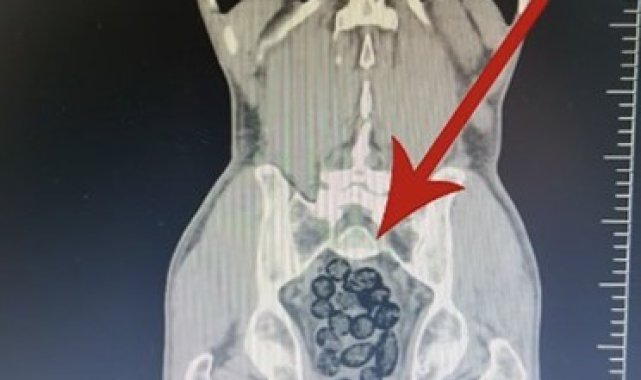

Batman'da durdurulan otobüsteki yabancı şahsın midesinden 64 parça uyuşturucu maddesi metamfetamin çıktı.Batman İl Emniyet Müdürlüğü Narkotik Suçlarla Mücadele Şube Müdürlüğü ekiplerince Batman Cumhuriyet Başsavcılığı koordinesinde yürütülen çalışmalar kapsamında Batman girişinde durdurulan otobüste arama yapıldı.Durumundan şüphelenilen yabancı uyruklu bir yolcu üzerinde arama yapıldı. Yapılan incelemeler sonucunda yabancı uyruklu şahsın midesinde 64 Parça halinde toplam 472 gram uyuşturucu maddesi metamfetamin olduğu belirlendi.Gözaltına alınan şahsın midesindeki uyuşturucu madde çıkartıldı. Emniyetteki işlemlerinin ardından adliye sevk edilen şahıs, çıkarıldığı mahkemece tutuklanarak cezaevine gönderildi.

Batman'da yabancı uyruklu bir şahsın midesinden 64 parça uyuşturucu çıktı

Batman'da durdurulan otobüsteki yabancı şahsın midesinden 64 parça uyuşturucu maddesi metamfetamin çıktı.